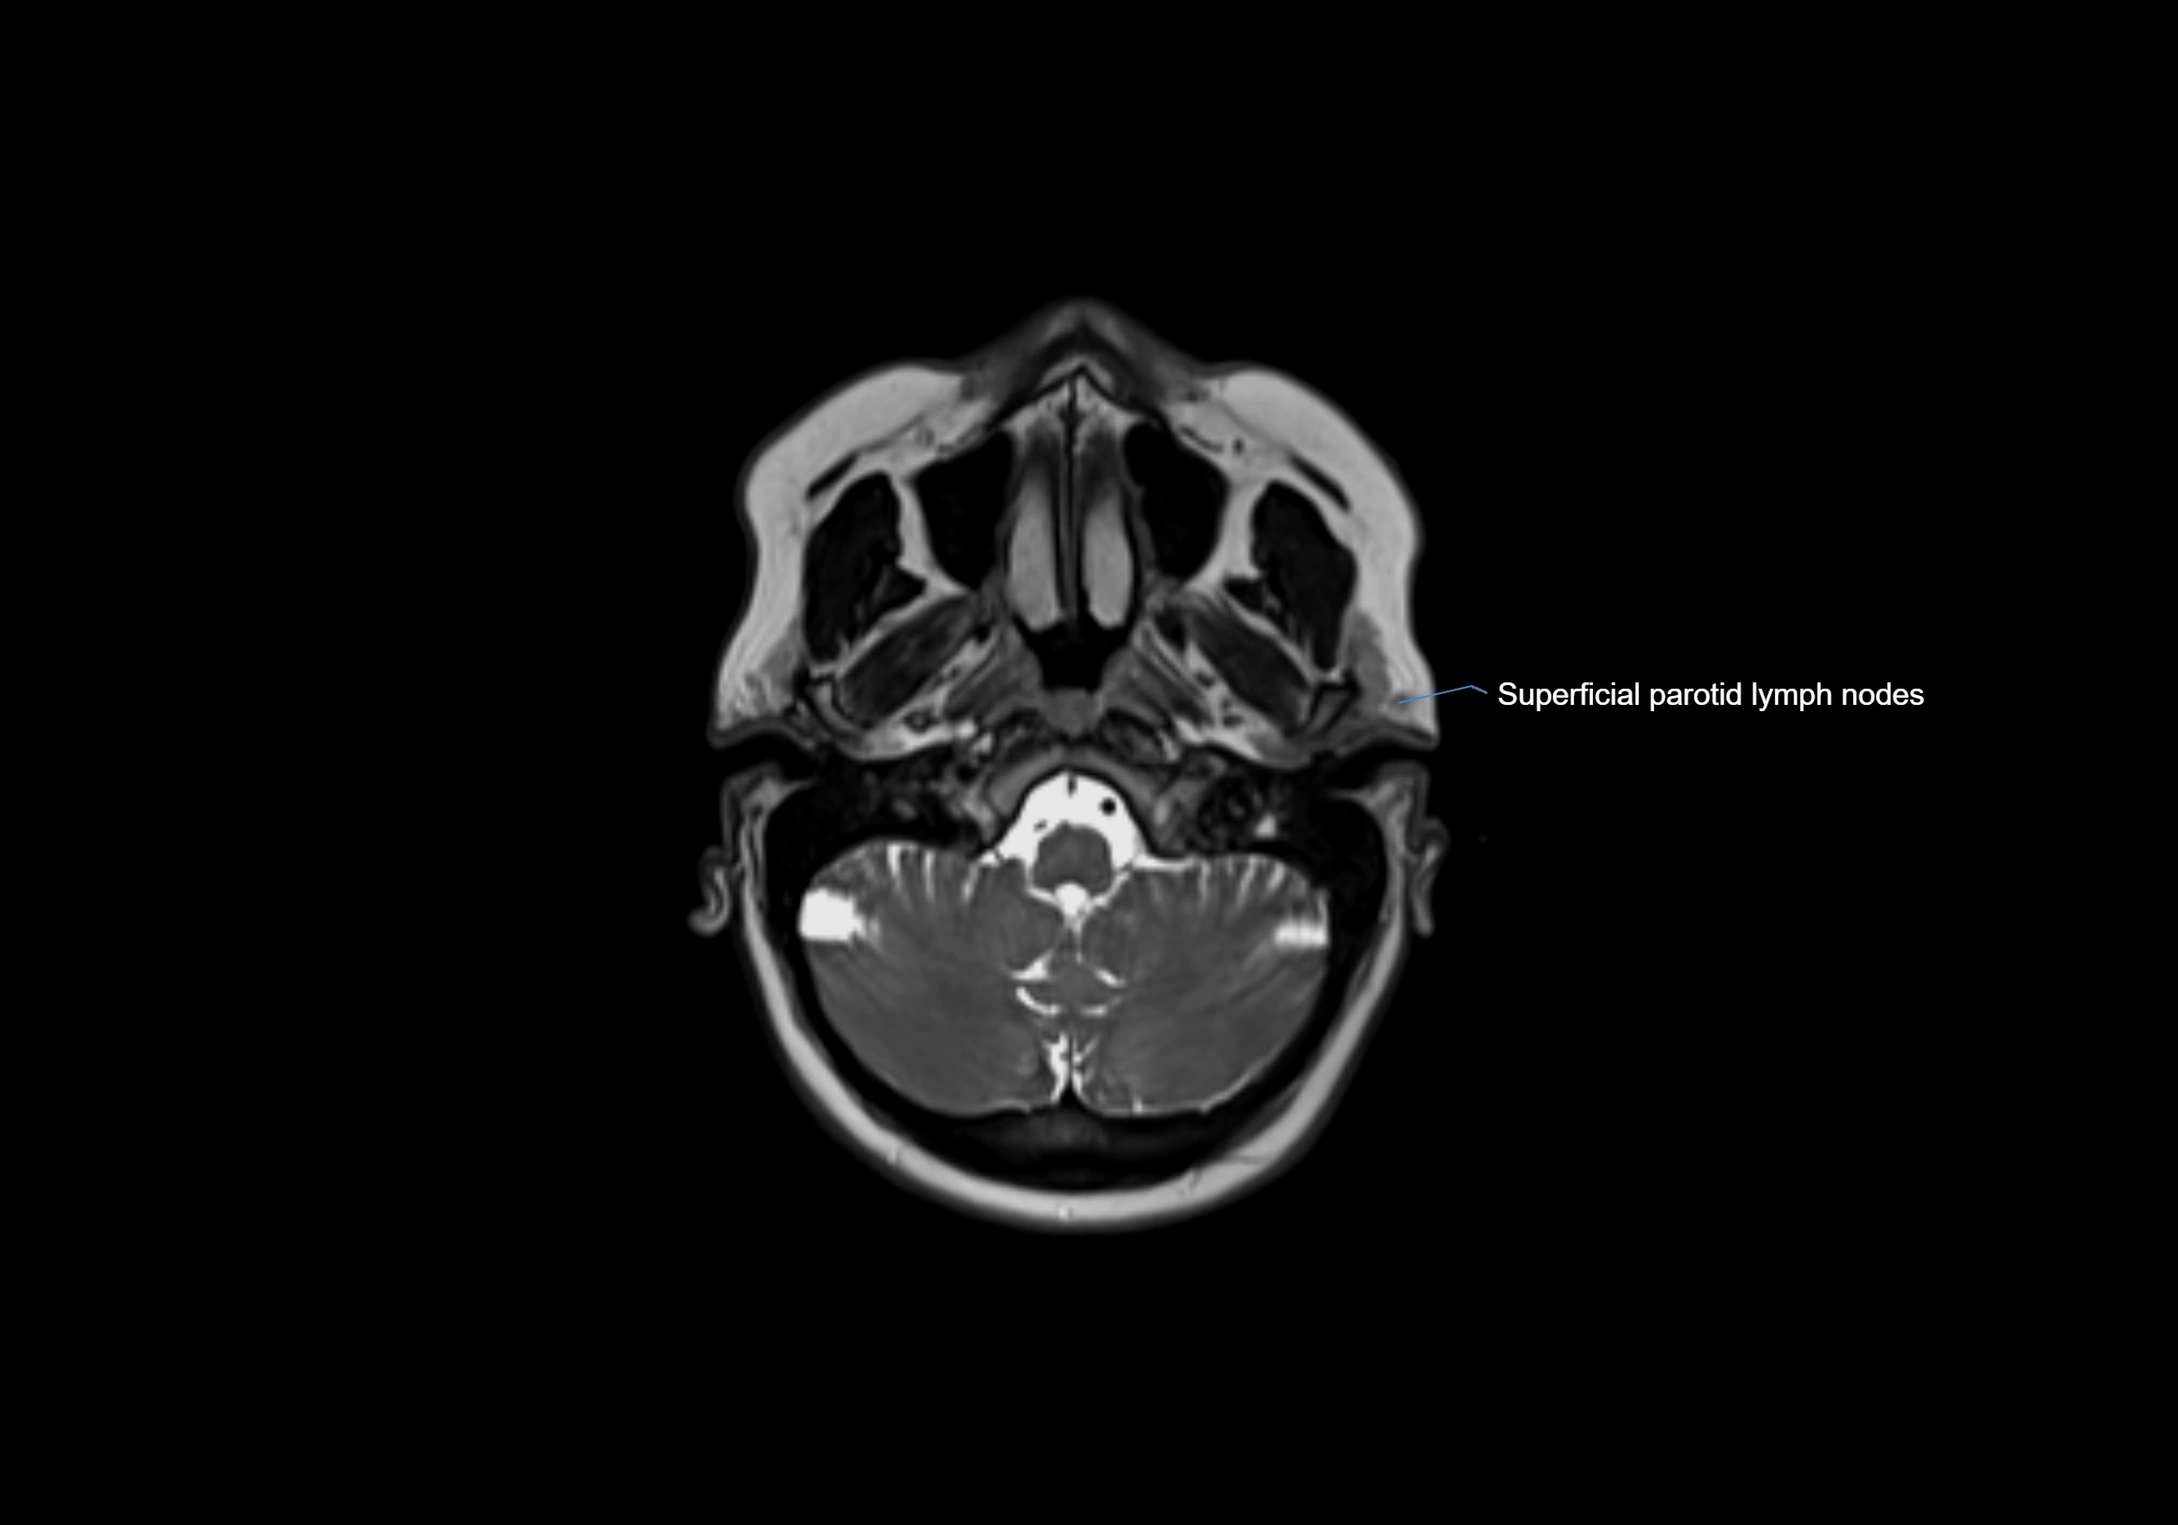

MRI Appearance

T2-weighted images:

• Nodes show intermediate signal, with surrounding fat bright

• Useful for detecting edema, inflammation, or infiltration

• Fatty hilum may appear slightly hyperintense relative to cortex

MRI images